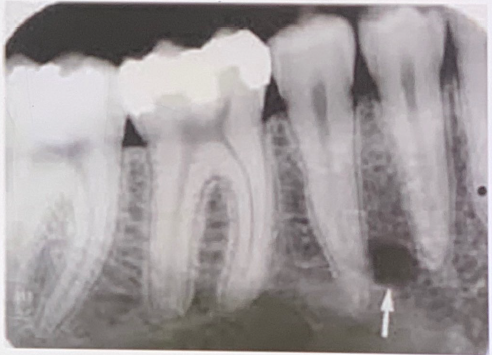

97. What is showing by arrow?

Nutrient Canals: carry a neurovascular bundle and appear as radiolucent lines of uniform width. most often seen on mandibular periapical radiographs running vertically from the inferior dental canal directly to the apex of a tooth or into the interdental space between the mandibular incisors. may appear as a small round radiolucency if they are oriented perpendicular to the cortex.